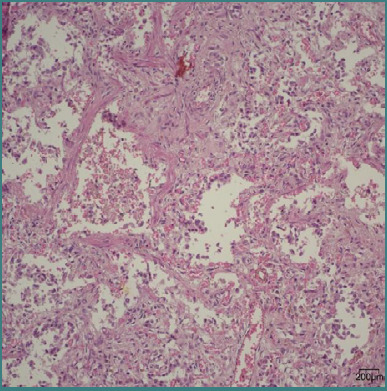

Preterm birth disrupts the natural progression of pulmonary development, which can trigger functional and morphological consequences that may lead to death or the development of a chronic lung disease. The objective of this research was to evaluate the pulmonary morphological characteristics in 67 preterm neonates who had survived for a minimum of 24 hours. All evaluations were carried out on paraffin-embedded lung tissue, sliced at 5 micrometers, and stained with a standard hematoxylin-eosin stain. From each case, photomicrographs of one square millimeter were assessed, and the quantity of alveoli, the diameter of the alveoli, the thickness of the alveolar septum, and the total thickness of the arteriolar and venular walls were measured. The research findings revealed that prolonged oxygen therapy has an impact on the density of alveoli per square millimeter in premature infants, regardless of their gestational age at birth. Additionally, neonates with lobar lung abnormalities exhibit a reduced number of alveoli per square millimeter. Moreover, preterm neonates delivered at extreme gestational ages demonstrated a notably reduced alveolar diameter compared to those born at more advanced gestational ages, and infants who developed bronchopulmonary dysplasia may exhibit increased alveolar septal thickness compared to other newborns.